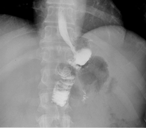

A giant duodenal diverticulum causing Lemmel syndrome

Roseanne Tobin and others

Journal of Surgical Case Reports, Volume 2018, Issue 10, October 2018, rjy263, https://doi.org/10.1093/jscr/rjy263